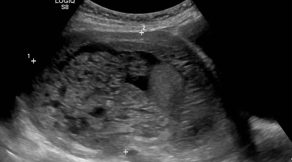

Miomas uterinos «Cuatro de cada cinco mujeres de entre los 30 y los 50 años presenta miomas uterinos».

Los miomas uterinos son masas anormales de tejido muscular liso que se localizan en y alrededor del útero y ocasionalmente en el cuello uterino. Estos miomas se originan de las células de músculo liso que existen en el miometrio o pared del útero. En la mayoría de los casos son múltiples, pero ocasionalmente pueden ser […]